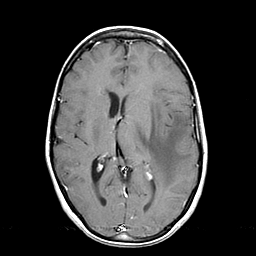

Metastatic bronchogenic carcinoma: T1-weighted MR -- Slice #12

[Home][Help][Clinical] Slice 12